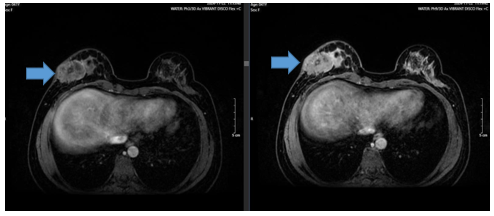

UNG THƯ BIỂU MÔ TẾ BÀO THẬN

Ung thư thận là loại ung thư thường gặp đứng thứ 14 trên toàn cầu, với hơn 430.000 ca mới được chẩn đoán vào năm 2020, và 434840 ca mắc trên toàn cầu vào năm 2022. Tỷ lệ mắc thay đổi theo khu vực địa lý, cao hơn ở châu Âu và Bắc Mỹ. Ung...